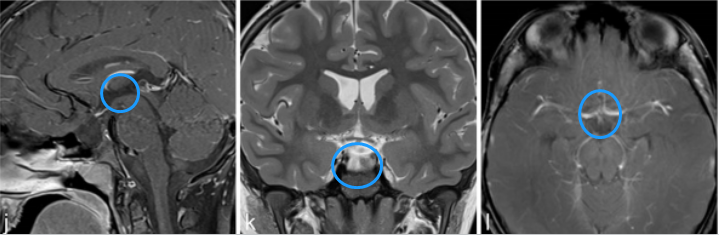

84岁女士视力减退。检查发现双侧视力下降、视野缺损。内分泌评估显示垂体功能完整。

a–c图中,MR成像显示鞍上部分实性,部分囊性对比增强病变,高度可疑的颅咽管瘤。

j-l图表示,在3个月后复查MR检查,显示术后垂体柄处有肿瘤少量残留。

m-o图显示,磁共振成像分期立体定向放射治疗后22个月,显示肿瘤明显缩小。病人经氢化可的松和甲状腺激素的替代治疗恢复良好。